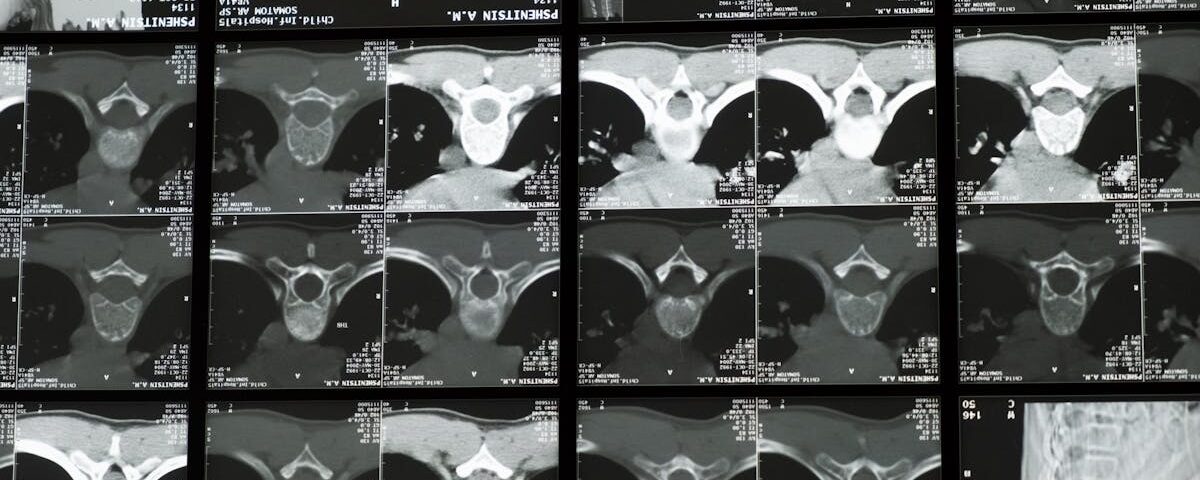

Dans cette catégorie, explorez une méthode innovante et non invasive pour soulager les maux de dos, qu’ils soient aigus ou chroniques. La décompression neurovertébrale cible les disques intervertébraux et les structures nerveuses comprimées, réduisant ainsi la pression, apaisant la douleur et favorisant la régénération des tissus. Nos articles mettent en lumière les bienfaits de cette thérapie de pointe, notamment l’amélioration de la mobilité, la réduction de l’inflammation et la prévention des complications à long terme. Basée sur des données scientifiques, cette approche offre une solution efficace et durable, intégrée dans une stratégie globale de gestion des douleurs dorsales pour améliorer la qualité de vie.